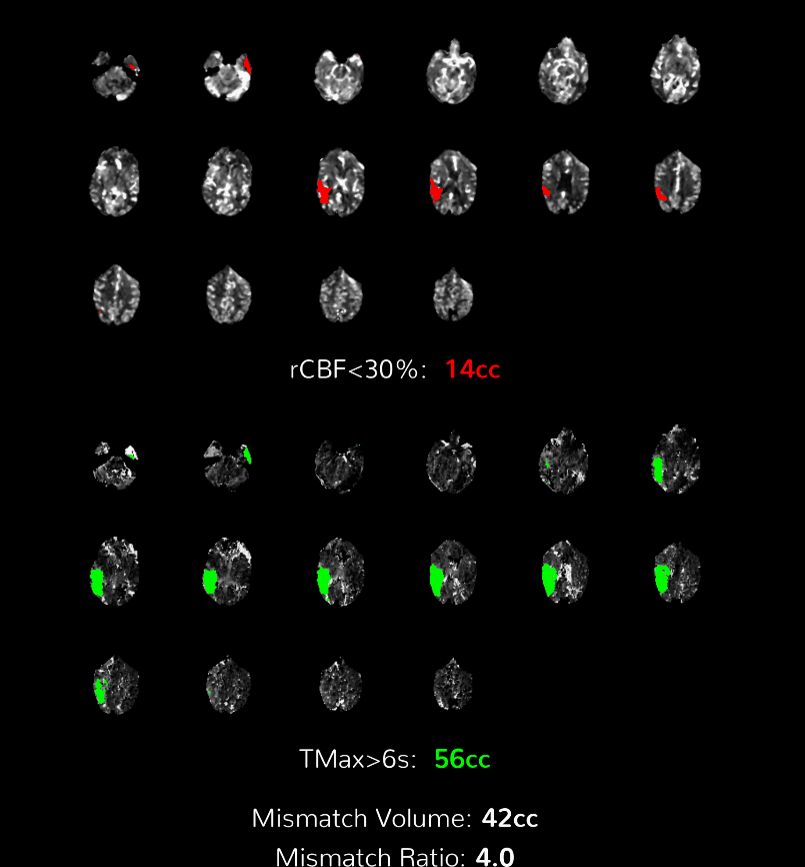

Perfusion